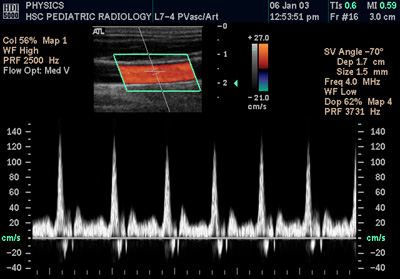

Clinical instruments integrate piezoelectric transducers developed from materials research at Bell Labs and University of Pennsylvania. Systems support continuous-wave and pulsed-wave modes, each influenced by developments at General Electric and Siemens Healthineers. Duplex ultrasound combines B-mode imaging innovations from Ultrasound Manufacturers Association with Doppler spectral analysis, while color Doppler overlays were popularized by commercial teams at Philips and Hitachi Medical. Advanced techniques include power Doppler—an adaptation of energy-based detection methods used in radar research at MIT Lincoln Laboratory—and tissue Doppler imaging, refined through collaborations among European Society of Cardiology funded research groups. Modern devices implement digital beamforming and real-time Fourier transforms influenced by computational advances at IBM and Intel.

Doppler ultrasound is central to Vascular surgery assessment of peripheral arterial disease, venous thrombosis evaluation in guidelines from American Venous Forum, and carotid stenosis detection referenced by European Society for Vascular Surgery. In Cardiology, transthoracic and transesophageal Doppler inform valve hemodynamics in practice at centers such as Cleveland Clinic and Mayo Clinic and underpin heart failure management per American Heart Association statements. In Obstetrics and gynaecology, uteroplacental and fetal Doppler surveillance is practiced in line with recommendations from International Federation of Gynecology and Obstetrics and Royal College of Obstetricians and Gynaecologists. Other fields employing Doppler include renal transplant surveillance in programs at Johns Hopkins Hospital, hepatic portal flow assessment in work presented at European Association for the Study of the Liver, and hemodialysis fistula evaluation supported by National Kidney Foundation guidance.

Interpretation and Diagnostic Criteria

Interpretation uses spectral waveforms, velocity measurements, and derived indices; peak systolic velocity thresholds for stenosis are included in consensus documents from Society for Vascular Ultrasound and European Society of Cardiology. Resistive indices applied in renal and transplant contexts refer to standards developed in multicenter studies involving institutions like Karolinska Institutet and University of Toronto. In obstetric surveillance, umbilical artery pulsatility indices are interpreted using centiles established by perinatal research networks led by MRC (United Kingdom) funded investigators. Diagnostic algorithms for deep vein thrombosis incorporate clinical decision rules from Wells family of studies and imaging protocols validated in trials at Massachusetts General Hospital.